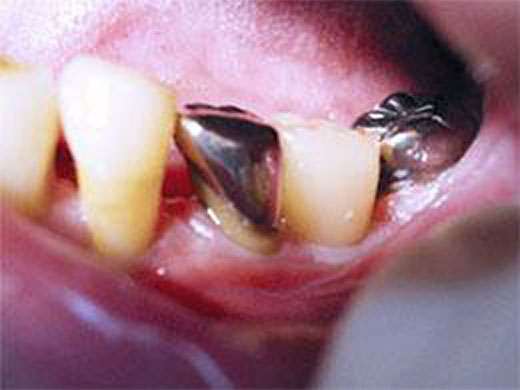

4. 一次手術(インプラント埋入)

局所麻酔をしっかりと効かせたうえで、インプラント本体(人工歯根)を顎の骨の中に埋め込みます。

切開はできるだけ小さく抑えるよう配慮し、術後の腫れや痛みを軽減できるように心がけています。

6. 上部構造(被せ物)の装着

インプラントと骨の結合が確認できたら、上部構造と呼ばれる被せ物を装着していきます。

噛み合わせを細かく調整し、周りの歯とのバランスや歯ぐきとの境目のなじみを確認しながら仕上げていきます。